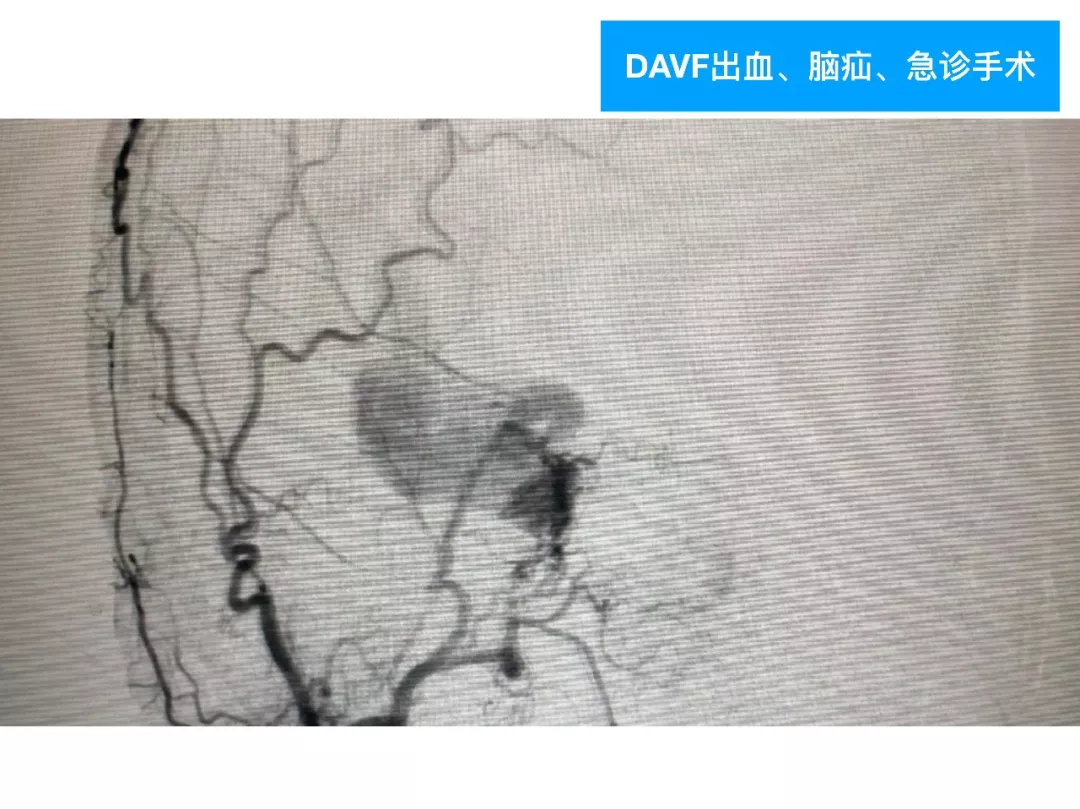

今天为大家分享的是《颅脑创伤-神经重症病例周刊》第四十九期,由天津市环湖医院神经外科五病区主任佟小光教授团队带来的:DAVF出血、脑疝急诊手术一例,欢迎阅读。

(2)DAVF即使术前很严重,及时闭塞DAVF,清除血肿,常常有好的预后;此例患者术前双侧瞳孔散大,术后回复超乎常规;

(3)对于此类DAVF,主要是蝶顶窦与海绵窦之间的逆流;扩大的中颅底入路,先闭塞引流入海绵窦的颈外动脉颌内动脉分支;然后将一侧海绵窦所有的漏口夹闭,切断所有的脑静脉与海绵窦逆流;

(4)虽然没有处理颈内动脉-海绵窦漏,在漏口闭塞后,所有的漏几乎都消失了。